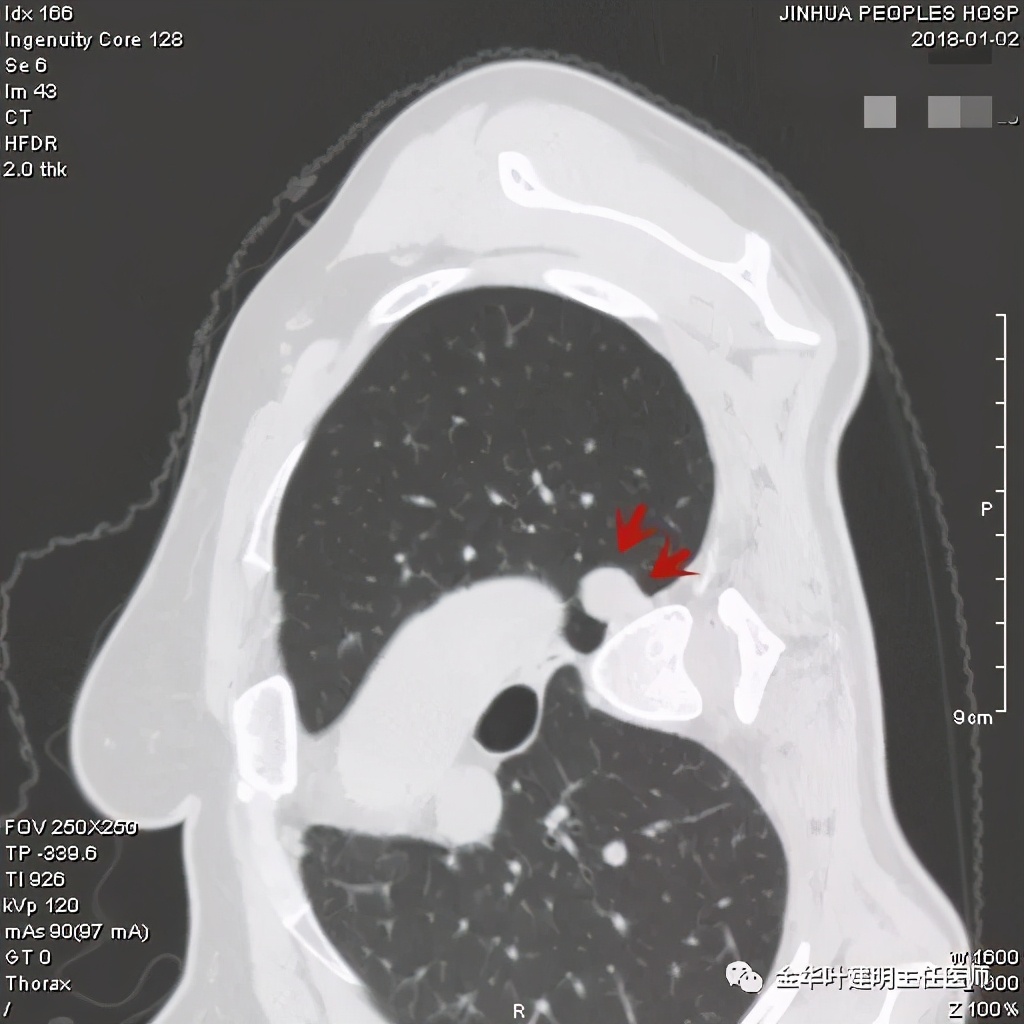

金华的某A,男性,70岁,因检查发现右上肺占位入院,没有临床症状,肿瘤筛查指标正常,血常规与CRP正常。胸部CT检查报告考虑恶性可能:

直径约2.4厘米,密度欠均,血管贴边,增强轻度强化。单从描述看,恶性可能性较大。我们再来看看图像:

可见右上叶占位,我们现在知道了结果以后回头看,发现病灶的边缘在各个层面都是过于光滑(绿色箭头所示)。血管紧贴病灶边走行(桔色箭头所指),是不是有侵犯看不清楚,若是靶扫描加重建可能会更清楚点。支气管感觉也是贴着病灶走,但有的层面是不是截断,也不看的不太清楚。有的层面见局部有点状高密度(蓝色箭头所指),是不是错构瘤的局部钙化呢?若是纵隔窗又是如何?